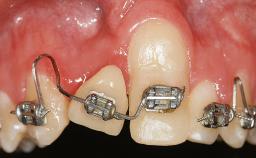

Adequate peri-implant soft-tissue thickness is essential not only for esthetic but also for functional reasons. In this case, Vincenzo Iorio Siciliano demonstrates how he achieved increased height and thickness of posterior peri-implant soft tissues to obtain a stable mucosal seal and a width of keratinized tissue favorable to toothbrushing.

The patient, a healthy 38-year-old woman, was referred for increasing the width of the keratinized tissues at the buccal aspect of dental implant 46. The site exhibited a premature-closure screw exposure caused by trauma during chewing, with inadequate keratinized tissue.